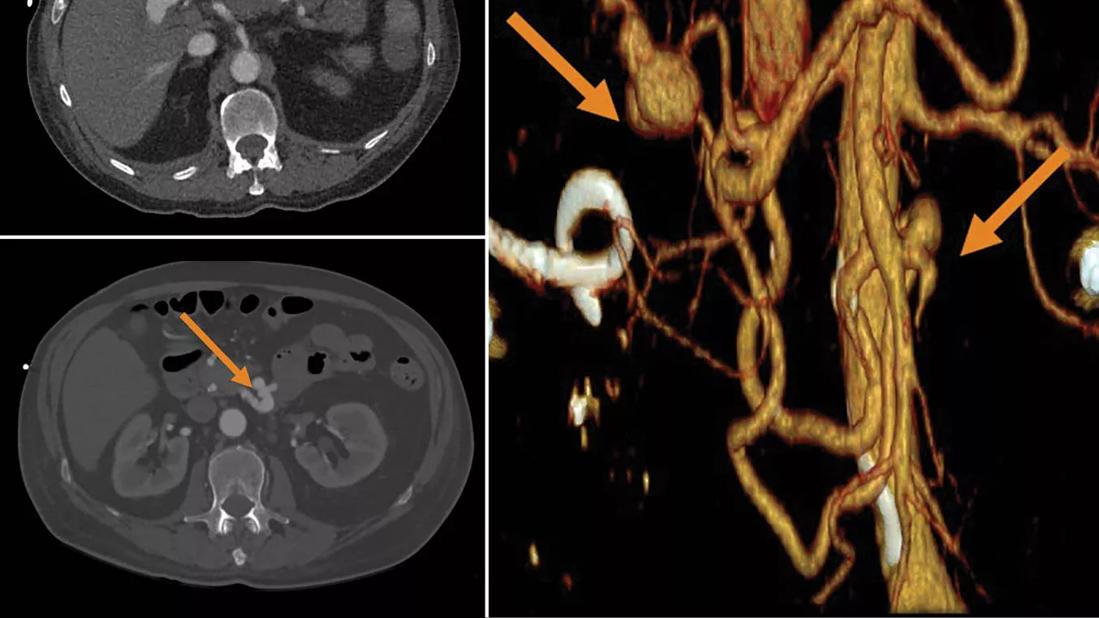

Top left: inferior pancreaticoduodenal artery aneurysm. Bottom left: distal right hepatic artery aneurysm. Right: distal right hepatic artery aneurysm and inferior pancreaticoduodenal artery aneurysm.

Imaging revealed hemorrhagic cholecystitis on right upper quadrant ultrasound with computed tomography arteriogram showing severe acute pancreatitis, 80% stenosis of the celiac artery at the origin, irregularity of the splenic artery without clear dissection, splenic infarction, a small aneurysm of the inferior pancreaticoduodenal artery, and a 3-cm aneurysm of the distal right hepatic artery.

He was diagnosed with endocarditis. Management included embolization of his right hepatic artery aneurysm by interventional radiology, redo aortic valve replacement and intravenous (IV) antibiotics for six weeks.